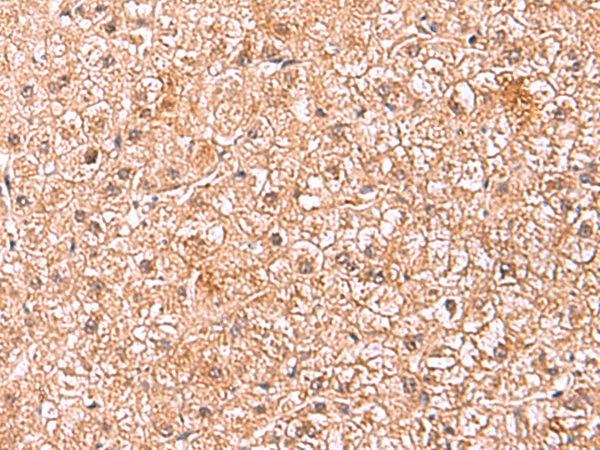

分类: 科研抗体货号: P10170别名: NML; KIAA0409应用: WB,IHC反应种属: Human, Mouse, Rat